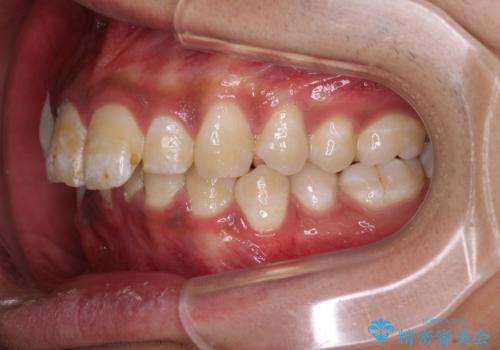

深い咬み合わせと前歯のデコボコ ワイヤー装置での抜歯矯正

- 深い咬み合わせと前歯のデコボコを改善したいとのことで来院された患者様です。

口元の突出感はないものの、上顎前歯のデコボコが著しく、右側の咬み合わせがずれていたため、上顎右側第一小臼歯1本を抜歯することとしました。

咬合力が非常に強く、抜歯したスペースがなかなか閉じないであろうことは予想できましたが、思っていた以上に期間がかかりました。

前歯のすり減りも著しかったため、仕上げの位置の調整にも期間を要しました。